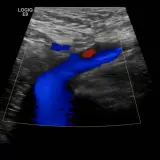

Casos totalmente interactivos con las herramientas que esperaría de un PACS: scroll, ventana, zoom, pan, mediciones, ROI y modo de pantalla completa.

• Anotaciones enlazadas

Anotaciones extensas resaltan los hallazgos clave directamente sobre los casos. Haga clic en los hallazgos enlazados dentro de la descripción del caso para saltar a su ubicación exacta en el estudio.

Desplace, arrastre, ajuste ventana y amplíe como en una estación PACS de trabajo

Aprenda con eficiencia gracias a hallazgos de imagen anotados e ilustraciones